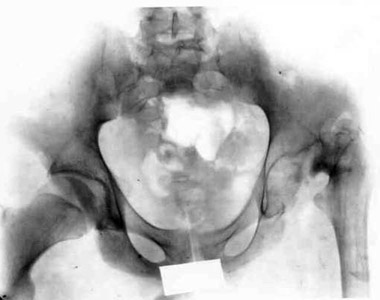

Defect of head and femoral neck of hip.

Defect of head and femoral neck of hip.Defect of head and femoral neck of hip.Defect of head and femoral neck of hip.